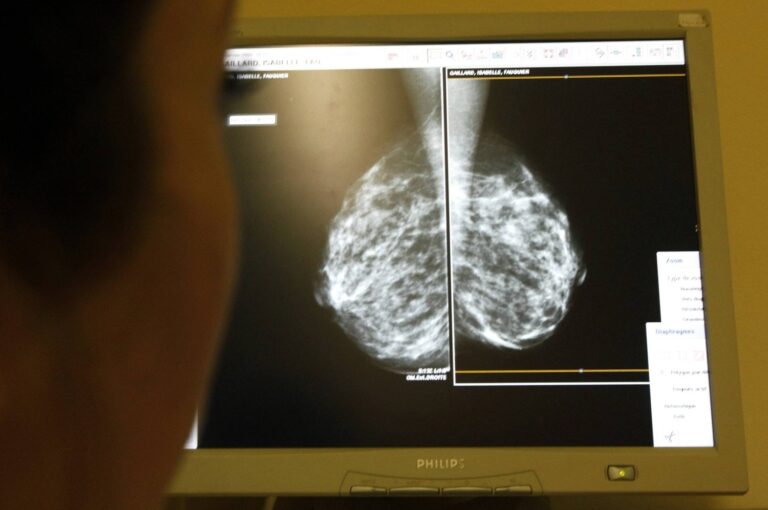

واحد من كل 726 رجلاً سيتم تشخيصهم بسرطان الثدي في حياتهم (أرشيفية - رويترز) صحة هل يصاب الرجال بسرطان الثدي؟ by admin 20 أكتوبر، 2024 written by admin 20 أكتوبر، 2024 462 واشنطن: «الشرق الأوسط» عندما يفكر الناس في سرطان الثدي، يفكر معظمهم في سرطان الثدي لدى النساء. لكن الحقيقة هي أن الرجال يصابون بسرطان الثدي أيضاً. ووفق تقرير نشرته شبكة «سي إن إن»، يشكل الرجال نحو 1 في المائة من جميع حالات سرطان الثدي، ما يعني أن 1 من كل 726 رجلاً سيتم تشخيصهم بسرطان الثدي في حياتهم. ويعدّ أحد أكبر التحديات المتعلقة بسرطان الثدي لدى الرجال هو أنه غالباً ما يمر دون أن يلاحظه أحد عموماً بسبب عدم وجود إرشادات فحص روتينية مثل تلك الخاصة بالنساء. يتم تشخيص أكثر من 40 في المائة من حالات سرطان الثدي عند الرجال في مراحل متأخرة (المرحلة 3 أو 4). ونتيجة لذلك، يحصل الرجال على علاجات أكثر قوة مقارنة بالنساء بسبب التأخير في التشخيص. قد تكون الأعراض خفية: كتل، إفرازات من الحلمة، تغيرات في الجلد، تورم حول منطقة الثدي. دور العوامل الوراثية في سرطان الثدي عند الرجال يمكن أن تؤدي الطفرات في جينات BRCA1 وBRCA2، التي ترتبط بشكل أكثر شيوعاً بسرطان الثدي والمبيض عند النساء، إلى زيادة خطر إصابة الرجل بسرطان الثدي. نحو 0.2 في المائة إلى 1.2 في المائة من الرجال الذين لديهم تغير متحور موروث في BRCA1 و1.8 في المائة إلى 7.1 في المائة ممن لديهم تغير متحور موروث في BRCA2 سيصابون بسرطان الثدي بحلول سن السبعين. على النقيض من ذلك، نحو 0.1 في المائة من الرجال في عموم السكان سيصابون بسرطان الثدي في نفس العمر. الرجال الذين لديهم طفرات في جين BRCA2 معرضون لخطر الإصابة بسرطان الثدي طوال حياتهم بنسبة تتراوح بين 7 في المائة و8 في المائة، وهي نسبة أعلى من عامة السكان من الذكور. لذلك، يجب على الرجال الذين لديهم تاريخ عائلي للإصابة بسرطان الثدي، وخاصة أولئك الذين لديهم طفرات في جين BRCA، أن يفكروا في إجراء اختبار جيني وأن يكونوا أكثر حساسية لأي تغيرات في أنسجة الثدي لديهم. مقارنة سرطان الثدي عند الرجال والنساء تتشابه سرطانات الثدي عند الرجال والنساء، ولكن هناك أيضاً بعض الاختلافات الرئيسية. نظراً لأن أنسجة الثدي عند الرجال أقل، فإن السرطان يكون غالباً أقرب إلى جدار الصدر، ما قد يؤثر على كيفية انتشاره. يبلغ معدل البقاء على قيد الحياة لمدة 5 سنوات للرجال المصابين بسرطان الثدي نحو 77.6 في المائة، مقارنة بـ86.4 في المائة عند النساء، ويرجع ذلك جزئياً إلى التشخيص المتأخر. ومع ذلك، فإن العلاجات (الجراحة والإشعاع والعلاج الكيميائي) هي نفسها إلى حد كبير بالنسبة للرجال والنساء. فحص ثديَي الرجل لا توجد إرشادات رسمية لفحص الثدي الذاتي للرجال، ولكن يمكن للرجال اتخاذ خطوات استباقية لمراقبة صحة ثديهم من خلال تقنيات الفحص الذاتي المقترحة. يُنصح بإجراء هذه الفحوصات في نفس الوقت كل شهر، ربما نفس وقت فحص الخصية الشهري. ابدأ بالوقوف عاري الصدر أمام المرآة لفحص أي تشوهات مثل التورم أو الكتل أو الغمازات أو تغيرات الحلمة، مع وضع ذراعيك على جانبيك ورفعهما فوق رأسك. لإجراء الفحص اليدوي، استلقِ مع وضع وسادة تحت كتفك وذراع الجانب الذي تفحصه خلف رأسك. استخدم اليد المعاكسة للضغط برفق بأصابعك في دوائر صغيرة عبر منطقة الثدي بالكامل والإبط، وتطبيق ضغوط مختلفة، واضغط برفق على الحلمة للتحقق من وجود إفرازات. إذا اكتشفت أي تغييرات، فاستشر مقدم الرعاية الصحية الخاص بك. ما يمكن للرجال فعله بشكل استباقي أهم شيء يمكن للرجال فعله هو الاهتمام بأجسامهم. إذا لاحظت أي كتل أو ألم أو تورم أو تغيرات في منطقة الثدي أو الصدر، فلا تتجاهلها. تحدث إلى طبيبك. وإذا كان لديك تاريخ عائلي للإصابة بسرطان الثدي أو البروستاتا، ففكر في إجراء اختبار وراثي. سرطان الثدي عند الرجال نادر، لكن هذا لا يعني أنه أقل خطورة. من خلال زيادة الوعي خلال شهر التوعية بسرطان الثدي، وكسر الوصمات وتشجيع الرجال على التحدث إلى أطبائهم، يمكن اكتشاف السرطان مبكراً. المزيد عن: السرطان 0 comment 0 FacebookTwitterPinterestEmail admin previous post تسريبات البنتاغون.. ماذا بعد إفشاء سرّ تل أبيب؟ next post تقنية «ليدار» ونظم الذكاء الاصطناعي تسرع وتيرة اكتشاف الآثار You may also like اختراق طبي: الذكاء الاصطناعي يكشف ألزهايمر بدقة غير... 11 مارس، 2026 طرق بسيطة لتخفيف أعراض التهاب المفاصل 11 مارس، 2026 سرطان الرئة الأكثر فتكا… والكشف المبكر ينقذ الآلاف 7 مارس، 2026 فتيات يقعن في فخ PPD مع موسم الحناء... 7 مارس، 2026 مفاجأة علاجية… عقار قديم يُظهِر فائدة جديدة للذاكرة 5 مارس، 2026 مسنون يقاومون الخرف: ما سر ذاكرتهم الخارقة؟ 4 مارس، 2026 تغييرات طفيفة في نمط الحياة تقلل من خطر... 26 فبراير، 2026 مارسه صباحاً ومساءً… نشاط يومي قد يبطئ السرطان 24 فبراير، 2026 (7 تغيرات) في الشخصية في منتصف العمر قد... 24 فبراير، 2026 التأمل مرتين يومياً قد يحدّ من تطور السرطان... 24 فبراير، 2026